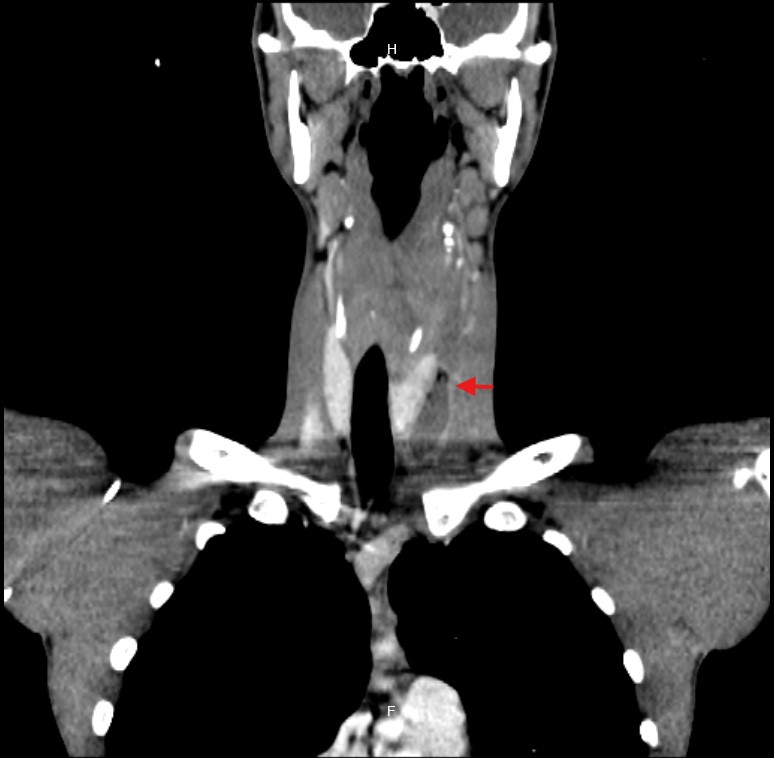

Due to the unclear etiology of the symptoms, combined with unremarkable initial studies and the subsequent development of dyspnea, a CT scan of the neck and thorax was performed. This revealed a large collection centered in the mediastinum, dissecting tissue planes and extending below the carina, reaching into the neck up to the left thyroid lobe. Gas was observed both within the collection and around the thyroid gland and mediastinum, with the esophagus displaced to the right by the mass effect of the abscess (Figure 1-5).

Figure 3 CT: Coronal view showing abscess in the left thyroid space.

Figure 4 CT: Coronal view showing cervicomediastinal abscess.

Figure 5 CT: Coronal view showing mediastinal abscess at the level of the bronchial bifurcation.